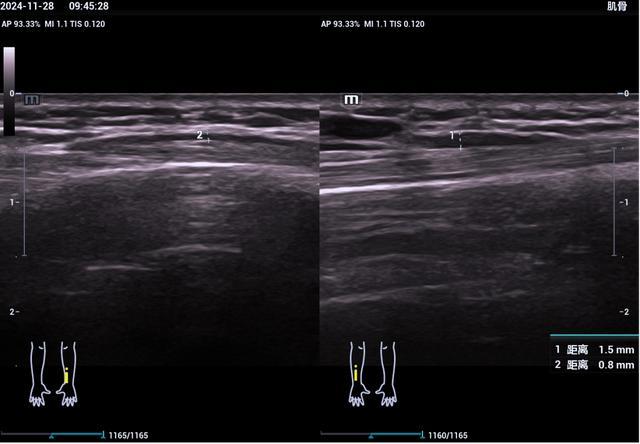

6、踝关节超声检查

踝管综合征、跟腱断裂、跟腱止点炎、崴脚后所致韧带损伤(距腓前韧带、跟腓韧带、胫腓前韧带、胫腓后韧带、距腓后韧带)、腓骨长短肌损伤、跖腱膜纤维瘤样增生、足底筋膜炎、痛风性关节炎等。